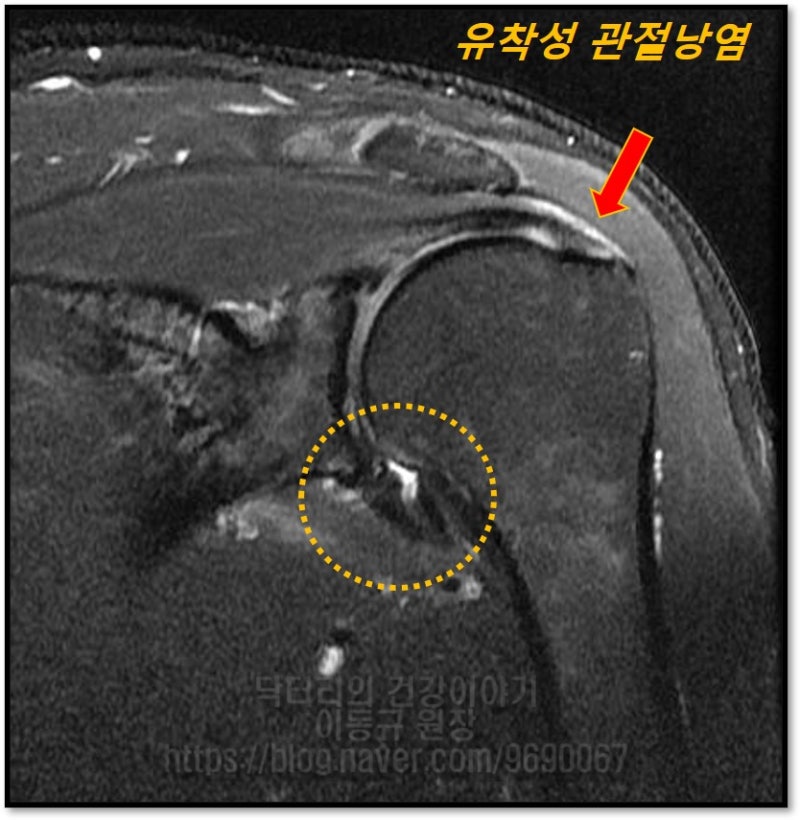

MRI 에서 주황색 원안에 관절낭이 유착되어 밴드처럼 두꺼워 진것이 관찰되며 빨간색 화살표에 보이듯 극상근의 부분적 손상과 염증 소견이 관찰됩니다.